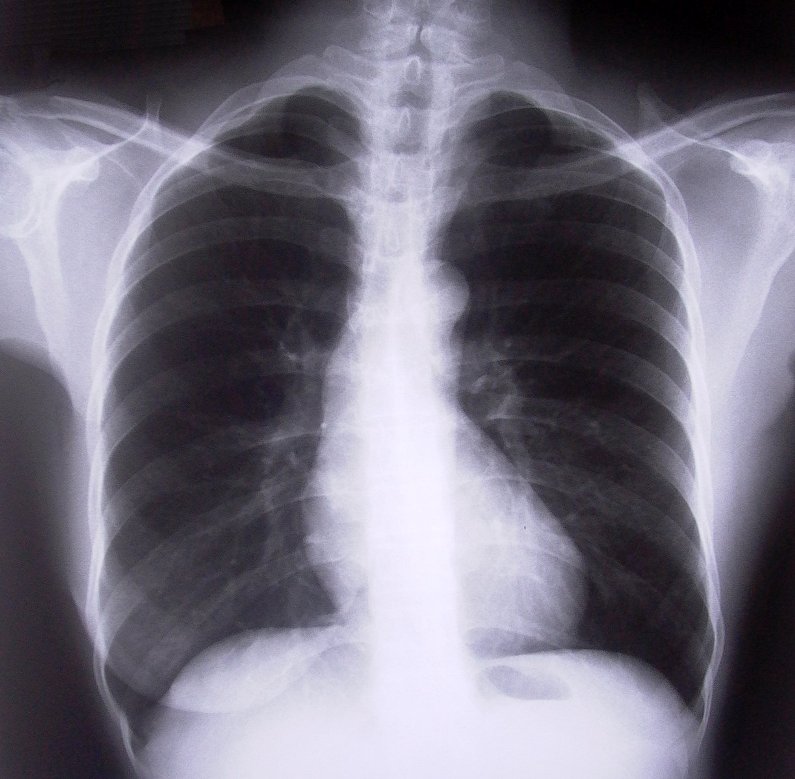

Nadciśnienie płucne (NP) jest rzadką, szybko postępującą, śmiertelnie niebezpieczną chorobą, która atakuje płuca i serce. NP to zespół objawów klinicznych spowodowanych wzrostem ciśnienia w krążeniu płucnym, czyli w obiegu krwi pomiędzy prawą komorą, płucami a lewym przedsionkiem serca. Istnieje kilka kategorii tej choroby, np. spowodowane wrodzoną wadą serca, czy występujące w przebiegu chorób płuc. Przewlekłe zakrzepowo-zatorowe nadciśnienie płucne oraz tętnicze nadciśnienie płucne są najgroźniejsze.

Nadciśnienie płucne to rzadka choroba, ale może na nią zachorować każdy. Często pojawia się bez przyczyny, a jej symptomy są najczęściej bagatelizowane – zarówno przez samych pacjentów, jak i lekarzy. Niejednokrotnie objawy są takie same, jak w przebiegu innych chorób, znacznie bardziej rozpowszechnionych: uczucie zmęczenia, znużenia, duszności, trudności w oddychaniu, zmęczenie przy pokonywaniu schodów, mozolne wykonywanie nawet najprostszych czynności domowych, zawroty głowy, suchy kaszel... Chorzy tłumaczą sobie swój stan przepracowaniem, brakiem snu, otyłością. A choroba postępuje – z każdym miesiącem jest coraz gorzej – pojawiają się obrzęki nóg, zasinienie ust, krwioplucie, zasłabnięcia. Dlatego nie należy lekceważyć nawet łagodnych objawów.

W przypadku NP nie można niestety mówić o zapobieganiu chorobie, dlatego tak ważne jest wczesne wykrycie i szybkie wdrożenie odpowiedniej terapii, bo blisko połowa nieleczonych pacjentów cierpiących na nadciśnienie płucne umiera w ciągu dwóch lat! Niestety, liczba chorych jest trudna do ustalenia. Postawienie prawidłowej diagnozy z uwagi na niespecyficzne objawy jest procesem trwającym nawet kilka lat. Tymczasem im wcześniej rozpocznie się leczenie, tym bardziej jest ono skuteczne. Aktualnie w Polsce leczy się około 1300 chorych cierpiących na tętnicze NP i przewlekłe zakrzepowo-zatorowe NP. Średnia wieku pacjentów to około 35 lat. Kobiety chorują dwa razy częściej niż mężczyźni. Również dzieci mogą być dotknięte tym schorzeniem.